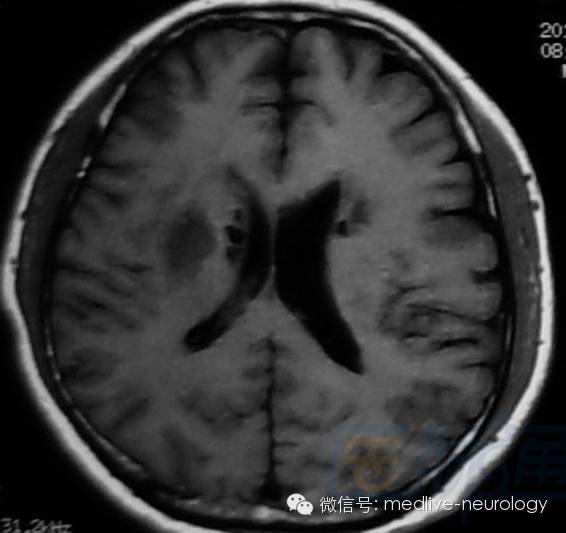

然后解决第三个问题,轻松一下,图来啦,让我们巩固一下今天学习的成果,均为先T1,后T2。

超急性期(<24h):右侧脑室旁